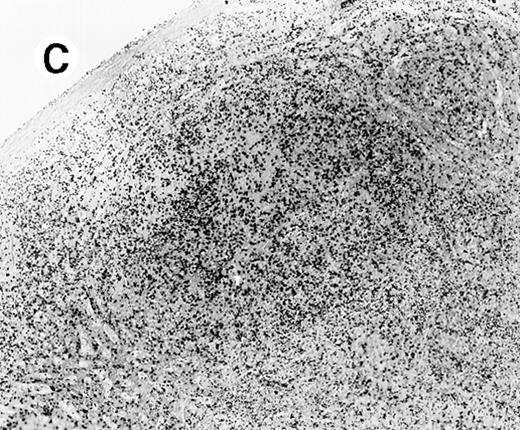

All cases showed essentially similar histologic findings in the liver and spleen. The splenic white pulp was inconspicuous to markedly depleted, whereas the sinusoids showed a prominent lymphoid infiltration (Figure 1A). There was striking hemophagocytosis within the splenic sinusoids (Figure 1B). The infiltrating lymphocytes were small and lacked significant cytologic atypia (Figure 1B). Immunoblasts and plasma cells were not prominent. The liver had prominent portal as well as sinusoidal infiltrates of small lymphocytes morphologically identical to those noted in the spleen (Figure 2). There was intracellular and intracanalicular cholestasis, steatosis, and focal necrosis. Hemophagocytosis was present within the sinusoids. In case 5, the spleen showed extensive areas of necrosis mainly in the perifollicular and periarteriolar lymphoid sheaths of the white pulp with the presence of immunoblasts reminiscent of IM.

Histologic findings in spleen.

(A) Section of spleen from case 2 shows depletion of white pulp and prominent sinusoidal small lymphoid infiltrates (hematoxylin and eosin, × 200). (B) The lymphocytes lack significant cytologic atypia. There is marked hemophagocytosis (hematoxylin and eosin, × 600).